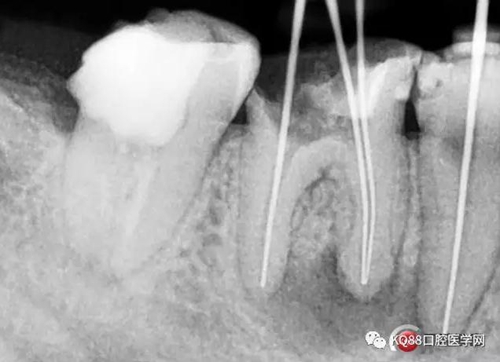

兩牙確定工作長(zhǎng)度